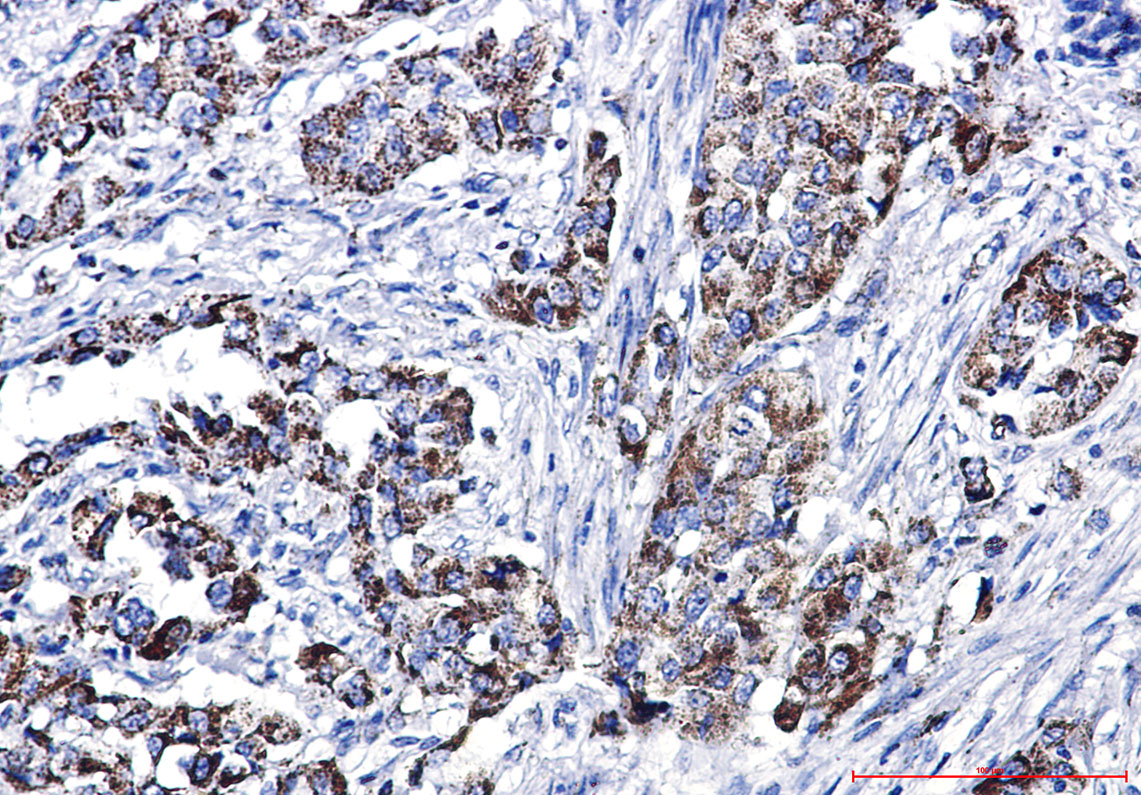

Immunohistochemistry analysis of paraffin-embedded Human lung cancer using Glutaminase antibody.High-pressure and temperature Sodium Citrate pH 6.0 was used for antigen retrieval.